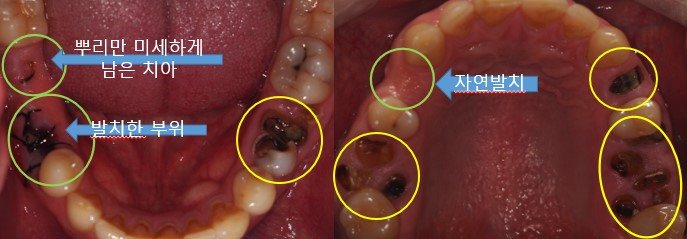

▲ 초진구강사진

충치로 인하여 뿌리만 남아있는 치아들과 심지어 자연 발치된 치아도 확인해 볼 수 있습니다.